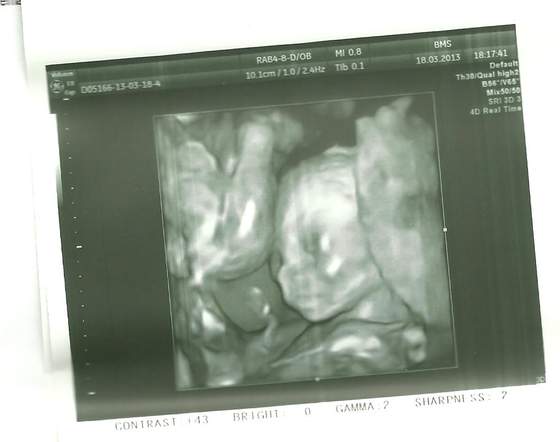

ale czadowo 2 w 1 :-) no no szczęściara miec od razu parkę gratuluje!!!Zobacz załącznik 546271Zobacz załącznik 546272A to moje maluszki:-)pierwsze to chłopczyk a na drugim dziewuszka:-)